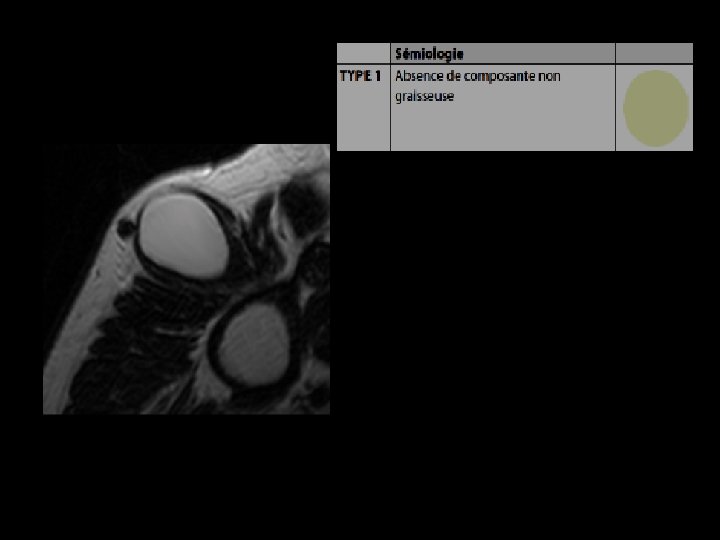

IRM: • Aspect tout à fait comparable à celui de la graisse souscutanée • Lésion homogène, hyperintense en pondération T 1 et T 2 • Séquences avec suppression du signal de la graisse : lésion hypointense

Comportement magnétique identique à celui de la graisse sous cutanée

Même type d’effacement de la graisse au sein de la masse et de la graisse sous cutanée

IRM : Cas particuliers • Capsule fibreuse en hyposignal sur l'ensemble des séquences • Fins septa réguliers conjonctivo-vasculaires, toujours d'épaisseur inférieure à 2 mm coupe axiale pondérée en. T 2 : visualisation de fins septa (flèches) au sein de la masse graisseuse homogène et en hypersignal